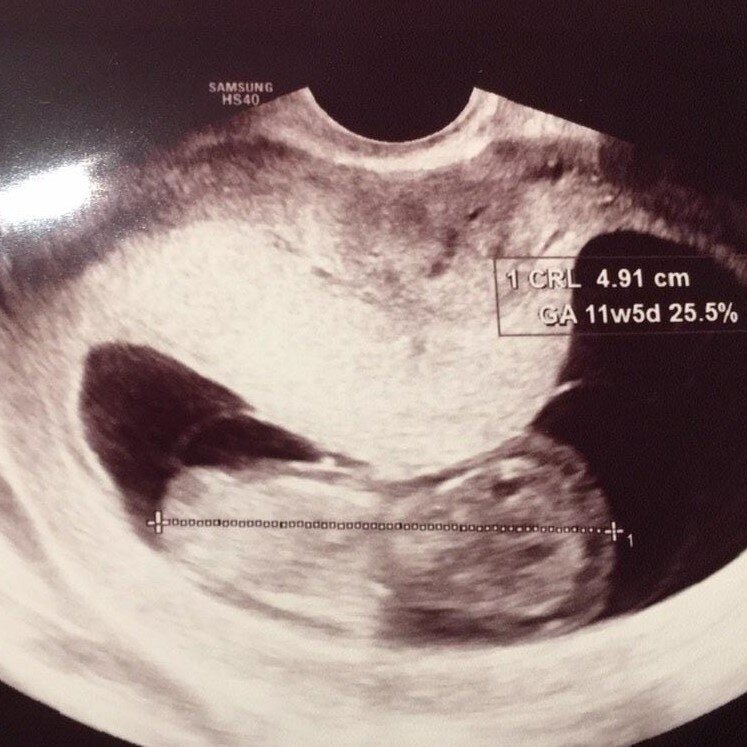

Ik stop met de anticonceptie en een aantal maanden later ben ik zwanger. Gewoon, vanzelfsprekend, alsof zo hoort dat te gaan, gelukkig. We krijgen een wolk van een dochter en 1,5 jaar later krijgen we er een zoon bij. Als onze zoon 2,5 is besluiten we om nog een poging te wagen, want hoe hectisch en druk het ook is, het is zo leuk! In twee maanden is het raak. Gewoon, weer, zomaar raak. Maar toch…. Een derde. Zo’n bewuste keuze, eigenlijk hebben we ‘alles al’  he… Twee gezonde kinderen, een dochter en een zoon, een koningskoppel, zo gemakkelijk gegaan. Zou je wel voor een derde moeten gaan? Dit gevoel bekroop mij. De eerste echo verwachtte ik niets te zien, want immers; drie keer geluk, dat kan haast niet. Maar jawel! Zes weken en een paar dagen, en een goed kloppend hartje! De termijnecho rond 11 weken gaf helaas aan dat het baby’tje even daarvoor gestopt was. Zie je wel… Alles wat volgt om een miskraam op te wekken zal ik even weglaten. In  ieder geval: ik was niet meer zwanger.

Vlak nadat we deze mooie ontwikkeling ontdekt hadden, gingen we twee weken op vakantie naar de Algarve (in Portugal). De vakantie was heerlijk ontspannen, maar ik was wel eenzaam met mijn alcohol. Mijn buik is op vakantie net zo hard gegroeid als die van mijn vrouw. Na terugkomst in Nederland hadden we 28 juni 2018 een echo ingepland staan en tijdens deze echo werd ons snel onze verrassing medegedeeld: “We waren niet zwanger  van één, maar van twee baby’s.” We hadden een 7-wekenecho en we kregen als officiële uitgerekende datum 11 februari 2019 te horen.  Omdat een tweeling altijd eerder komt, hopen we de 37 weken wél te halen. Alles voor de 37 weken wordt namelijk gezien als prematuur.